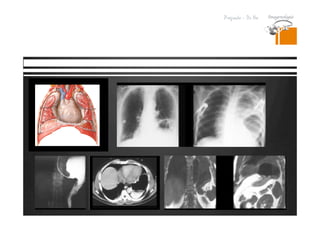

Lesiones isodensas en TC.

RESONANCIA MAGNETICA

DR. JULIO LAMA